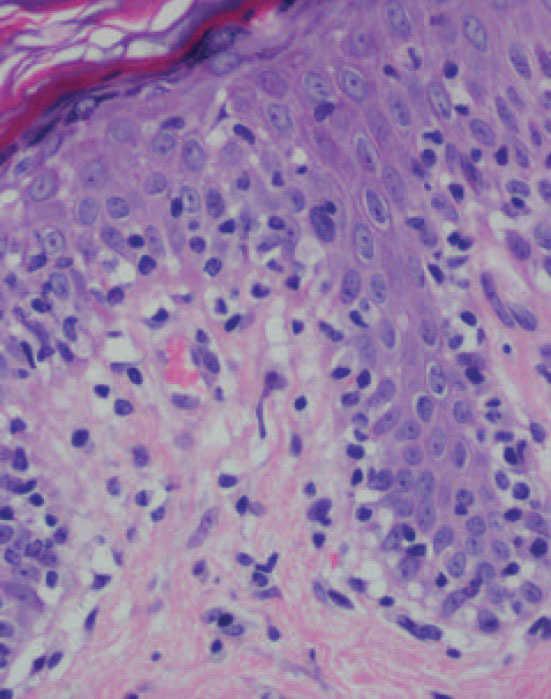

Se practicaron varias biopsias cutáneas, algunas de ellas sin alteraciones significativas. En otras se observó (figs. 4-6) una epidermis con hiperqueratosis y paraqueratosis focal, elongación de las crestas interpapilares y focos de degeneración hidrópica basal, con algún cuerpo apoptótico aislado. En dermis superficial y media existía un infiltrado linfocitario perivascular. Llamaba la atención la exocitosis de linfocitos atípicos intraepidérmicos, alguno de ellos con halo claro perinuclear y en alguna zona incluso iniciando la formación de microabscesos de Pautrier.

Como ocurrió con nuestro paciente, el estudio histopatológico en los estadios iniciales de la enfermedad puede ser muy inespecífico, lo que motiva además el retraso diagnóstico. En las fases más avanzadas revela la presencia de epidermotropismo de linfocitos anómalos, que a veces constituyen microabscesos de 5,6,8,11-23. En contraste con la micosis fungoide clásica, en esta variante parece que se observa un epidermotropismo más llamativo en contraste con un infiltrado linfocitario moderado en la dermis24.

Fig. 5.—Exocitosis intraepidérmica de linfocitos atípicos. (Hematoxi-lina-eosina, ×100.)

Fig. 6.—Exocitosis linfocitaria que muestra degeneración hidrópica basal. (Hematoxilina-eosina, ×100.)